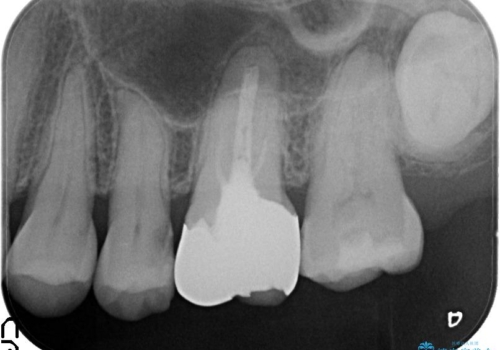

金属をセラミックにしたい、根管治療も行ったケース

左上6の金属のかぶせものをセラミックにかえるにあたり、根管治療からやり直しています。

基礎工事と同じで、歯の治療においても見えるところを白くきれいにするだけではなく、根管治療をしっかり行うこともとても大切です。